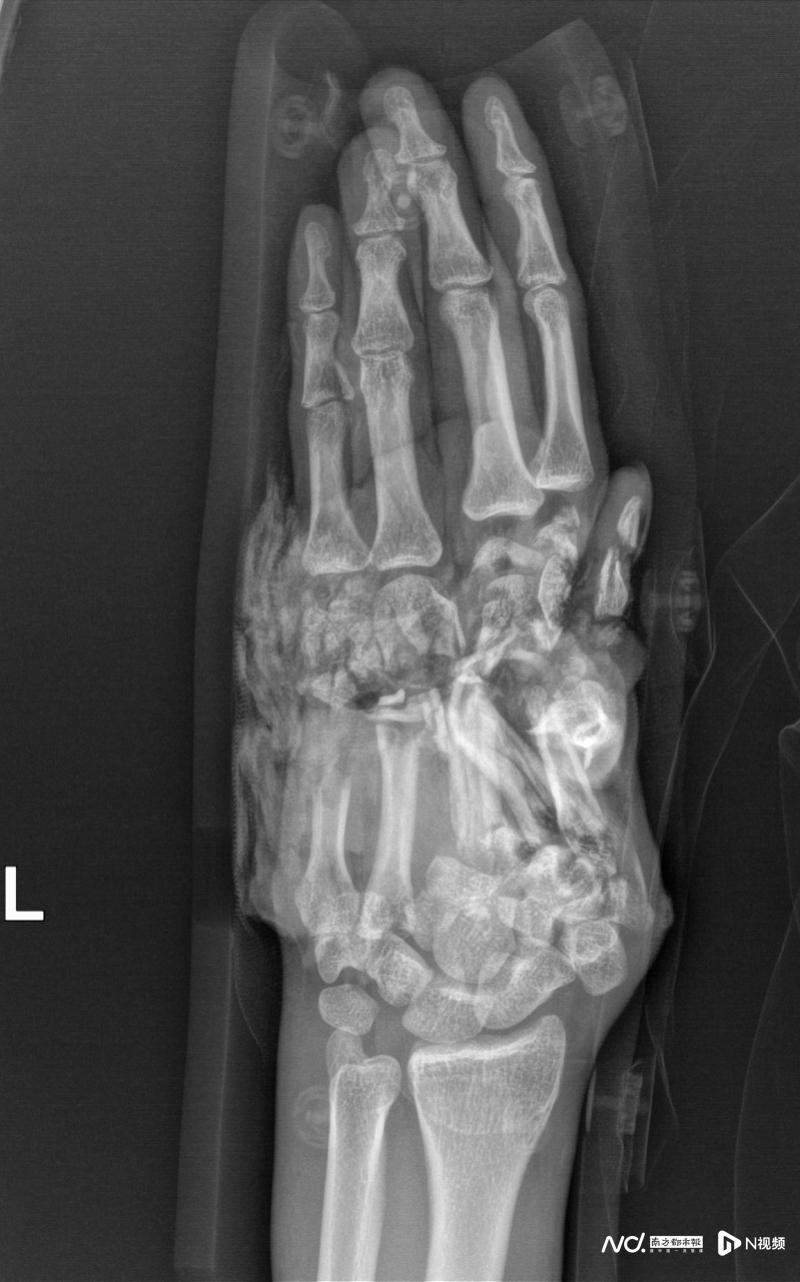

影像檢查提示,傷者的左手掌已經(jīng)被巨大的力量毀損得支離破碎。

當(dāng)?shù)蒯t(yī)院緊急包扎后,醫(yī)生坦言傷勢過重?zé)o法處理。王先生當(dāng)即決定轉(zhuǎn)院,于當(dāng)天上午11點多抵達(dá)廣州和平骨科醫(yī)院。創(chuàng)傷顯微外一科主任王小立團(tuán)隊接診時發(fā)現(xiàn),患者左手1-5掌骨粉碎性骨折,手背及腕部皮膚大面積撕脫,血管、神經(jīng)、肌腱多處斷裂,創(chuàng)面污染嚴(yán)重。“左手已因失血和創(chuàng)傷瀕臨壞死,保肢難度極大。”參與救治的何天頌醫(yī)生回憶,但患者保肢意愿極其強(qiáng)烈:“無論如何,請你們試一試!”